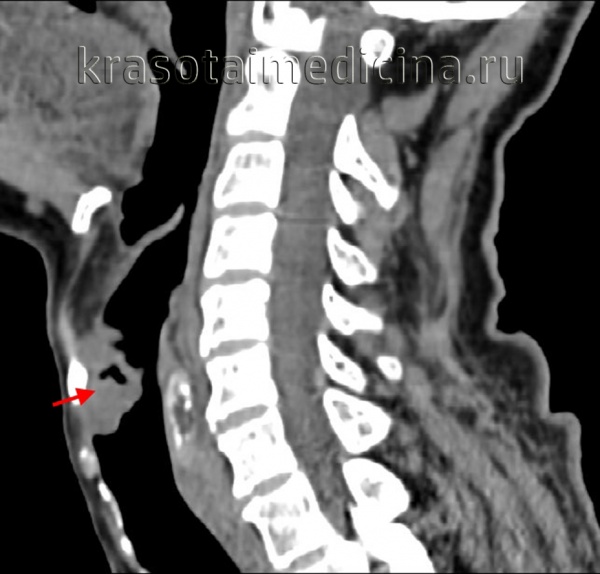

Определение распространенности опухоли уха проводится при помощи КТ черепа, КТ и МРТ головного мозга, ангиографии, фарингоскопии и других обследований.